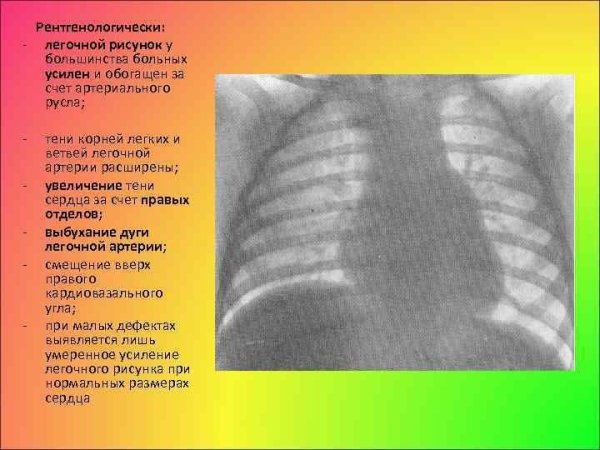

Усиление сосудистого рисунка легких у ребенка может быть признаком различных патологий и состояний. Это визуальное изменение на рентгеновских снимках обычно связано с увеличением притока крови в сосуды легких, что может указывать на наличие воспалительных процессов, инфекций или аллергических реакций. Также это наблюдается при повышении давления в легочной артерии, что может быть вызвано сердечными заболеваниями или другими патологиями системы кровообращения. В любом случае, обнаружение усиленного сосудистого рисунка легких у ребенка требует дополнительного обследования и консультации с педиатром или пульмонологом для постановки точного диагноза и назначения соответствующего лечения.